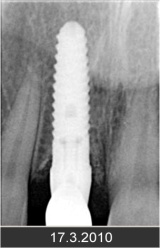

Klasickým příkladem a indikací pro použití implantátu je ztráta jednoho zubu (v tomto případě v předním – frontálním úseku) v jinak zdravém, nepoškozeném chrupu.

Nejčastější příčinou takové ztráty je sportovní nebo dopravní úraz.

Náhrada jednoho zubu pomocí implantátu je možná také v postranním úseku chrupu. Při ztrátě většího počtu zubů ve frontálním nebo postranním úseku může být mezer uzavřena větším počtem jednotlivých implantátů.